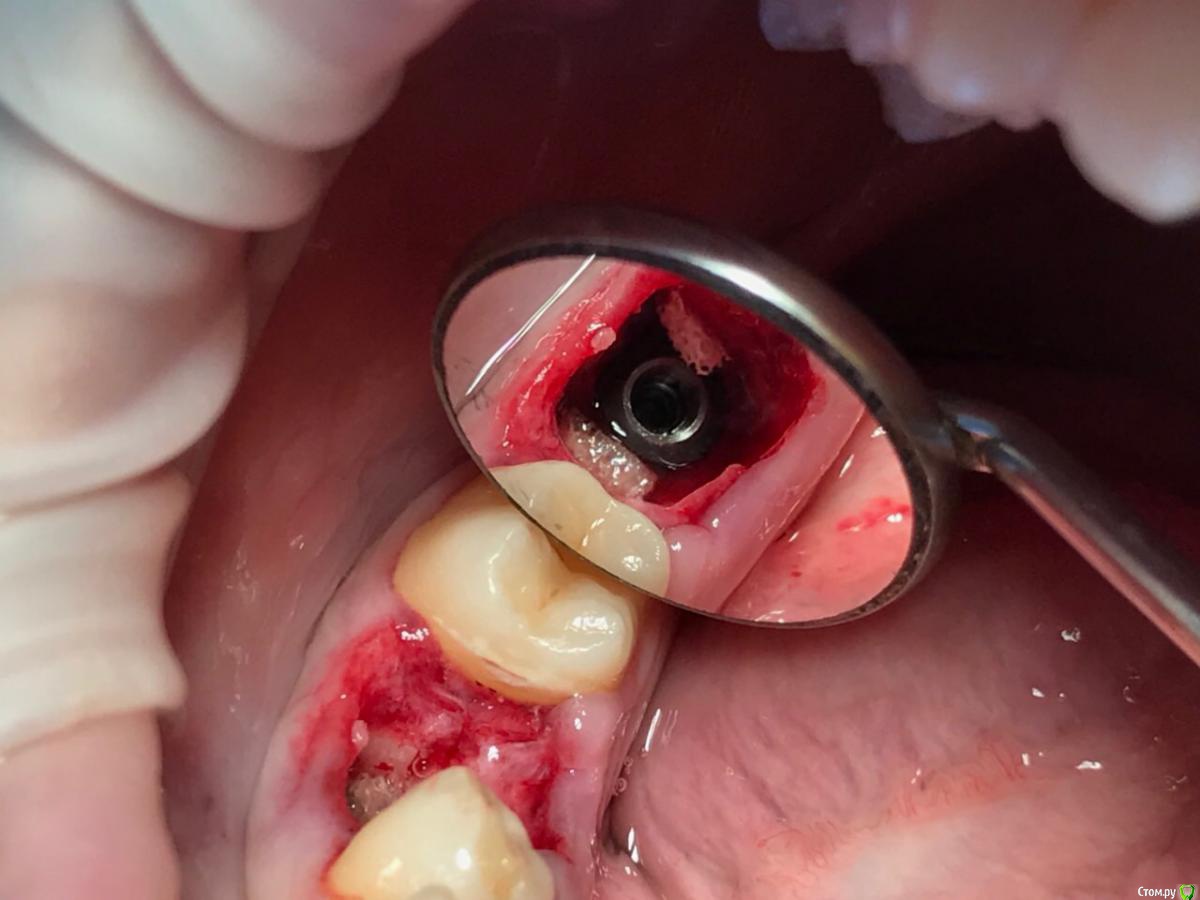

dr.Dre Опубликовано 14 июля, 2018 Поделиться Опубликовано 14 июля, 2018 Добрый вечер,коллеги такая ситуация разработал лунку под имплант , 2-3 витка при установке не доходит, пркручиваеться, извлёк имплант засверлился глубже тоже самое, в чем причина незнаю.Импланты megagen,icx active Ссылка на комментарий

dr.Dre Опубликовано 15 июля, 2018 Автор Поделиться Опубликовано 15 июля, 2018 Камрад, а челюсь то какая и картику имплантата покажи, че за зверь?нижня челюсть , megagen 6,0 Ссылка на комментарий

dr.Dre Опубликовано 15 июля, 2018 Автор Поделиться Опубликовано 15 июля, 2018 В этот раз глушить, а в следующий перед сверлением ложа примерять сначала фрезу руками.Сильно он не крутился поставил формик Ссылка на комментарий

gum Опубликовано 16 июля, 2018 Поделиться Опубликовано 16 июля, 2018 Надо было апикально на 1 или даже на 2 размера сверла меньшего диаметра использовать. И фиксировать имплантат за счет апикальной части. По крайней мере с Эниридж всегда работает. Здесь форма имплантата немного похожа. Ссылка на комментарий